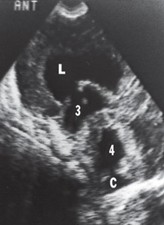

1. Hydrocephalus is a dilation of the ventricles due to an excess of CSF that may result from either a blockage of CSF circulation or, rarely, an overproduction of CSF (e.g., due to a choroid plexus papilloma). There are two general categories of hydrocephalus:

1. Communicating (or nonobstructive) hydrocephalus. In this type of hydrocephalus, there is free communication between the ventricles and the subarachnoid space. The blockage of CSF in this type of hydrocephalus is usually in the subarachnoid space or arachnoid granulations and results in the enlargement of all the ventricular cavities as well as the subarachnoid space. The sonogram below shows the dilated lateral ventricle (L) communicating through a dilated foramen of Monro with a dilated third ventricle (3) and dilated fourth ventricle (4). The cisterna magna (C) is also shown.

Communicating (or nonobstructive) hydrocephalus.

1. Noncommunicating (or obstructive) hydrocephalus. In this type of hydrocephalus, there is a lack of communication between the ventricles and the subarachnoid space. The blockage of CSF in this type of hydrocephalus is in the foramen of Monro, the cerebral aqueduct, or the foramen of Magendie/foramina of Luschka and results in the enlargement of only those ventricular cavities proximal to the blockage. There are two types of congenital hydrocephalus, both of which produce a noncommunicating (obstructive) hydrocephalus:

• Congenital aqueductal stenosis (Figure 7.30) is the most common cause of congenital hydrocephalus. This type may be transmitted by an X-linked trait, or it may be caused by cytomegalovirus or toxoplasmosis. The sonogram (Figure 7.30) shows dilated lateral ventricles (L), dilated third ventricle (3), but normal-size fourth ventricle (4). Therefore, obstruction at the cerebral aqueduct is presumed.

Congenital aqueductal stenosis.